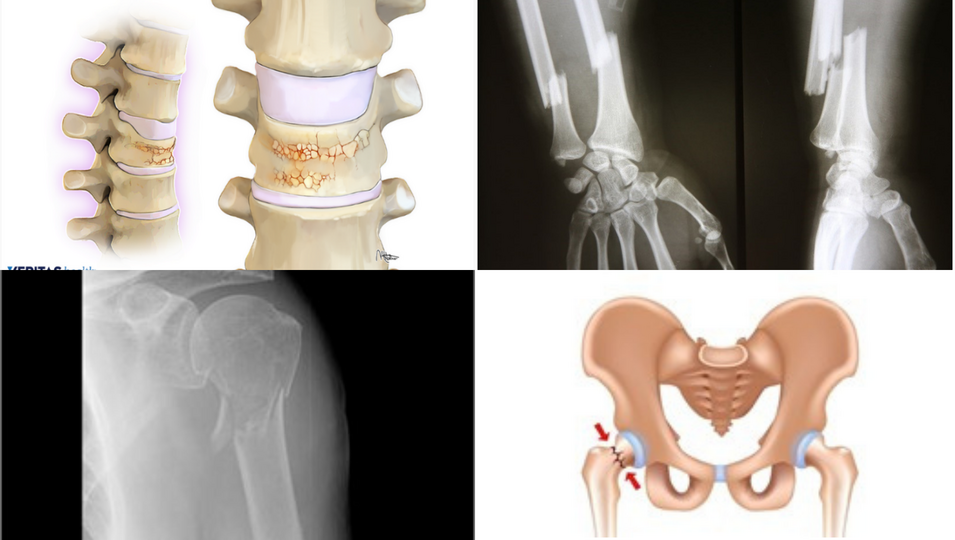

The 4 most common osteoporotic fracture sites:

• Back bone (spinal/vertebral) fracture/crumbling

• Wrist (radius) fracture

• Shoulder (humerus) fracture

• Hip fracture

Collage of diagrams of the effects of osteoporosis on the spine and the hip, and x-ray images of broken arms due to osteoporosis